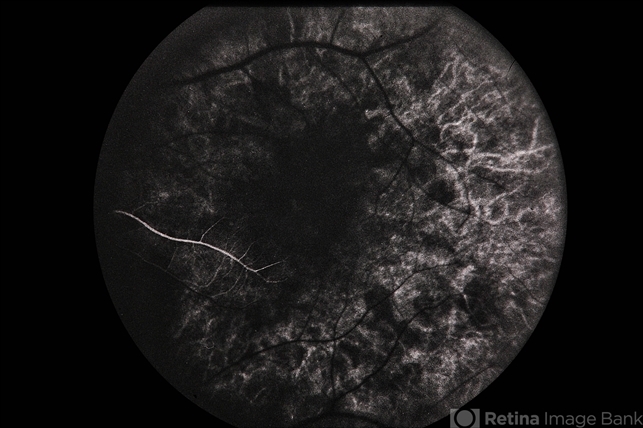

- XLinked Retinoschisis Female

- Condition/keywords

- x-linked retinoschisis (XLRS)

- 34-year-old white female, x-linked retinoschisis.